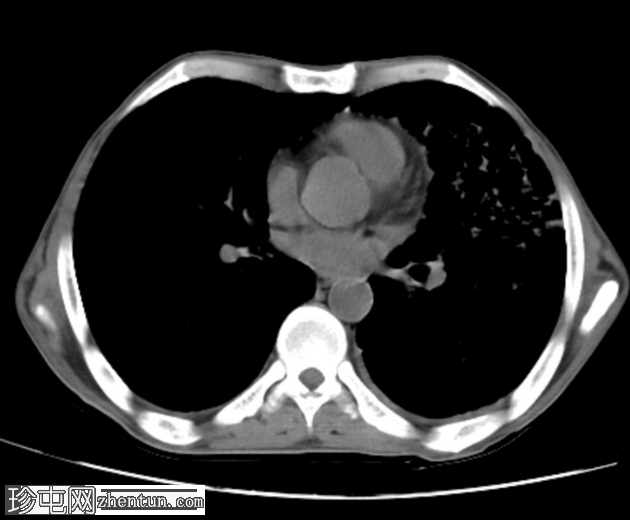

轴向非造影

CT扫描图像:双侧肺部广泛粟粒性结节。

双侧肺部广泛粟粒性结节及树芽征,伴左上叶空洞及小气腔实变。

该病例的放射学检查结果高度提示结核病,尤其是粟粒性结节和椎体受累(结核性椎间盘炎)。

粟粒性疾病是由血源性播散至肺部和其他器官所致,其特征是多个2-3毫米的小结节,随机分布。小叶间隔增厚和细小的小叶内网络通常较为明显。